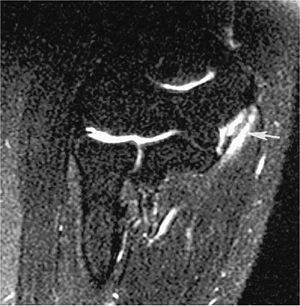

![]() |

FIGURE 8-39 Ulnar neuritis. Axial T1- (A) and T2- (B) weighted images showing an enlarged ulnar nerve (arrow) with increased signal intensity on T2-weighted image (B).